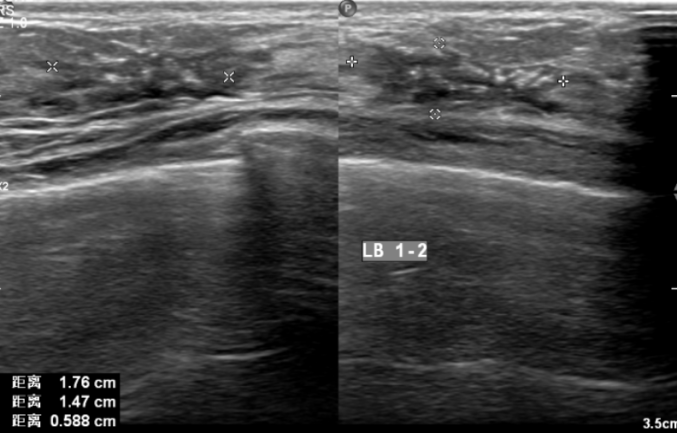

2021-7-29乳腺B超提示:左侧乳腺1-2点钟A环内见大小约21*22*8mm低回声区,边界不清,内见散在强光点,周边可见血流信号。余双侧乳腺腺体形态、结构未见异常。

左侧腋窝见多枚低回声结节,边界清,形态饱满,有包膜,较大者约16*7mm,内可见血流信号。右侧腋窝见多发低回声结节,边界清,有包膜,较大者约10*4mm,血流信号不明显。

影像诊断:左侧乳腺低回声区(BI-RADS:6类);左侧腋窝淋巴结偏大。

图3.乳腺B超(2021-7-29)

2021.9.9乳腺B超提示:左侧乳腺1-2点钟A环内见大小约18*15*6mm低回声区,边界不清,内见散在强光点,周边可见血流信号。余双侧乳腺腺体形态、结构未见异常。

两侧腋窝可见多枚低回声结节,边界清,有包膜,左侧较大者约9*5mm,右侧较大者约10*4mm,血流信号不明显。

影像诊断:左侧乳腺低回声区(BI-RADS:6类);两侧腋窝多枚淋巴结显示。

图4.乳腺B超(2021-9-9)